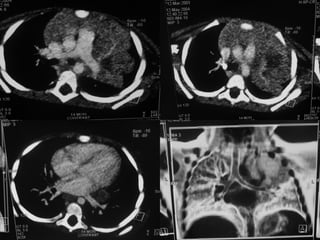

ΥΤ και εισρόφηση ξένου σώματος

Όταν υπάρχει κλινική υποψία

Αρνητικές α/ες

Αρνητική πρώτη βρογχοσκόπηση

Για την εκτίμηση επιπλοκών

Πνευμομεσοθωράκιο-Πνευμοθώρακας

Πνευμονία-Ατελεκτασία

Βρογχεκτασία

Εμπύημα-φλεγμονή θωρακικού τοιχώματος

Για την ανάδειξη άλλων αλλοιώσεων

ΥΤ θώρακα: προσφέρει?